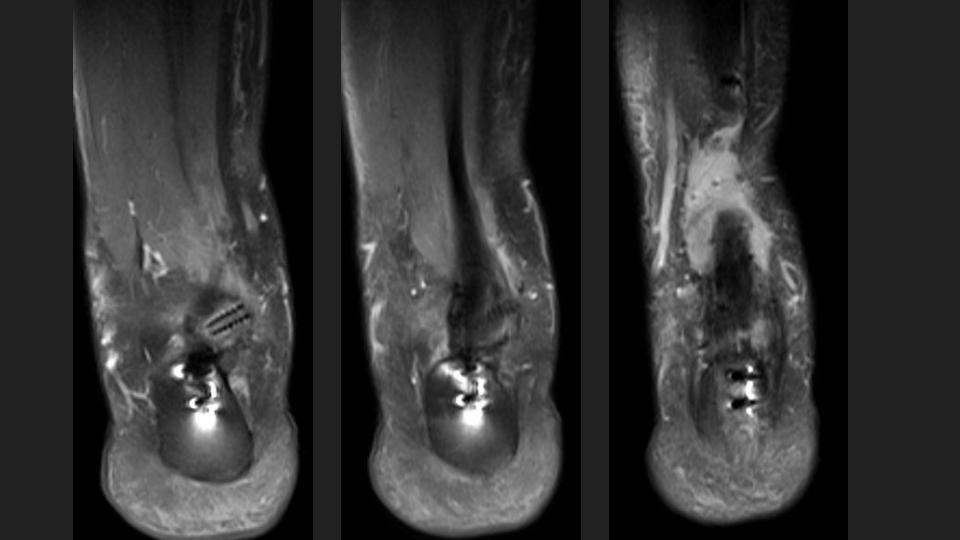

Sag PDFS

Cor T2FS

Ax PDFS

The referrer requested assessement of Achilles (specified “posterior tendon”) healing, now 8 months after FHL transfer for Achilles rupture.

In the T1-weighted image you can see a healed calcaneal osteotomy, and there is suture artifact around the distal achilles, related to a more remote Haglund’s procedure which pre-dated the complete tendon rupture in the hypovascular zone.

Now 8 months out, there is some intrasubstance bright T2 signal at the anterior insertion of the FHL onto the posterosuperior calcaneus, surrounding a bioabsorbable screw, possibly reaction to the screw degradation.

I am both surprised that the referrer wants to evaluate healing of the native achilles, and that there is persistent bright T2 signal in a >3cm achilles defect so long after the initial injury.